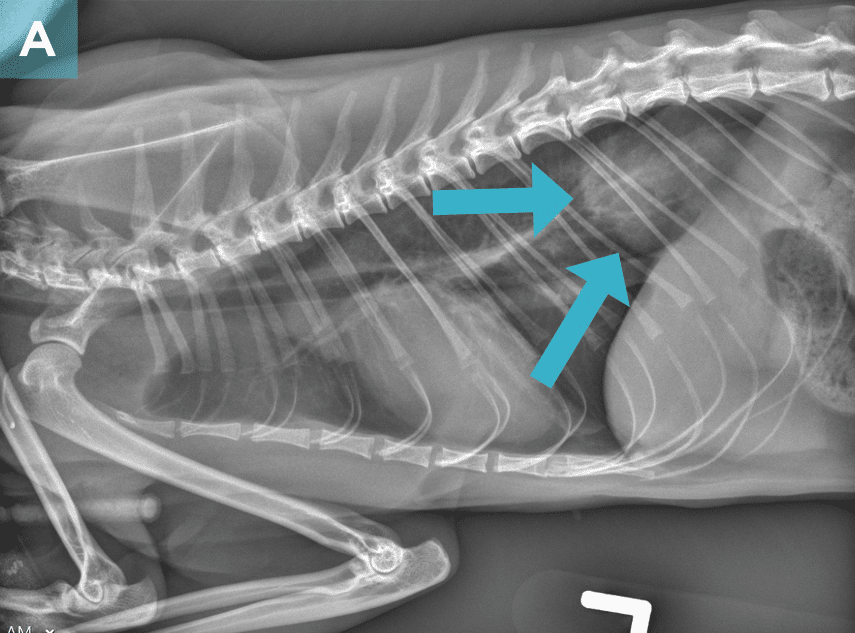

On survey thoracic radiographs, the heart and lungs were normal. A soft tissue opacity in broad-based contact with the diaphragm was noted in the caudal thorax (FIGURE 2), and the intra-abdominal portion of the stomach was shifted slightly cranially and to the left; findings were consistent with a hiatal hernia. The cat was anesthetized for computed tomography (CT) of the head and possible surgery.